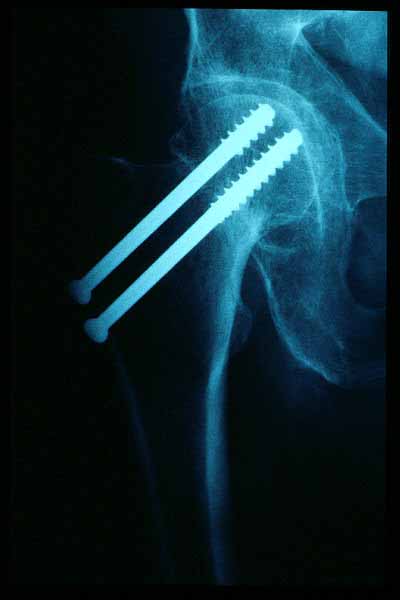

Fractura intertrocantérea de fémur, osteosíntesis